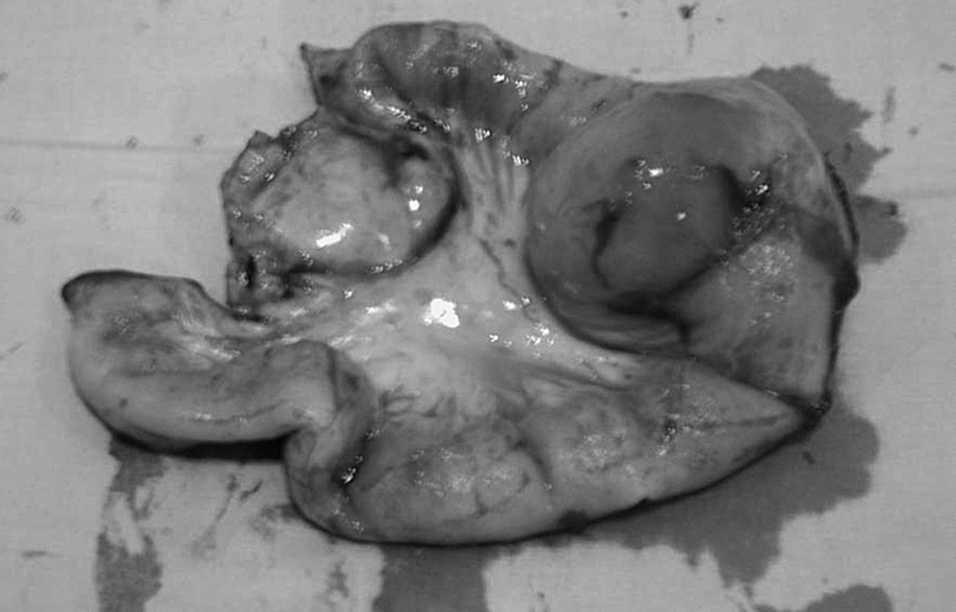

Tras traslado (3-11-2007) al servicio de cirugía general, el 7-11-2007 se practica laparotomía exploradora, previa transfusión de dos concentrados de hematíes el día previo a la intervención por hemoglobina de 7. Se realiza laparotomía media, con el hallazgo de un tumor de intestino delgado (figs. 1 y 2) a unos 50 cm de la válvula ileocecal, con grandes adenopatías principales, que se extirpan junto con la pieza quirúrgica; se realiza anastomosis mecánica laterolateral.

Fig.1.Pólipo inflamatorio fibroide (tamaño).

Fig.2.Pólipo inflamatorio fibroide (visión lateral).